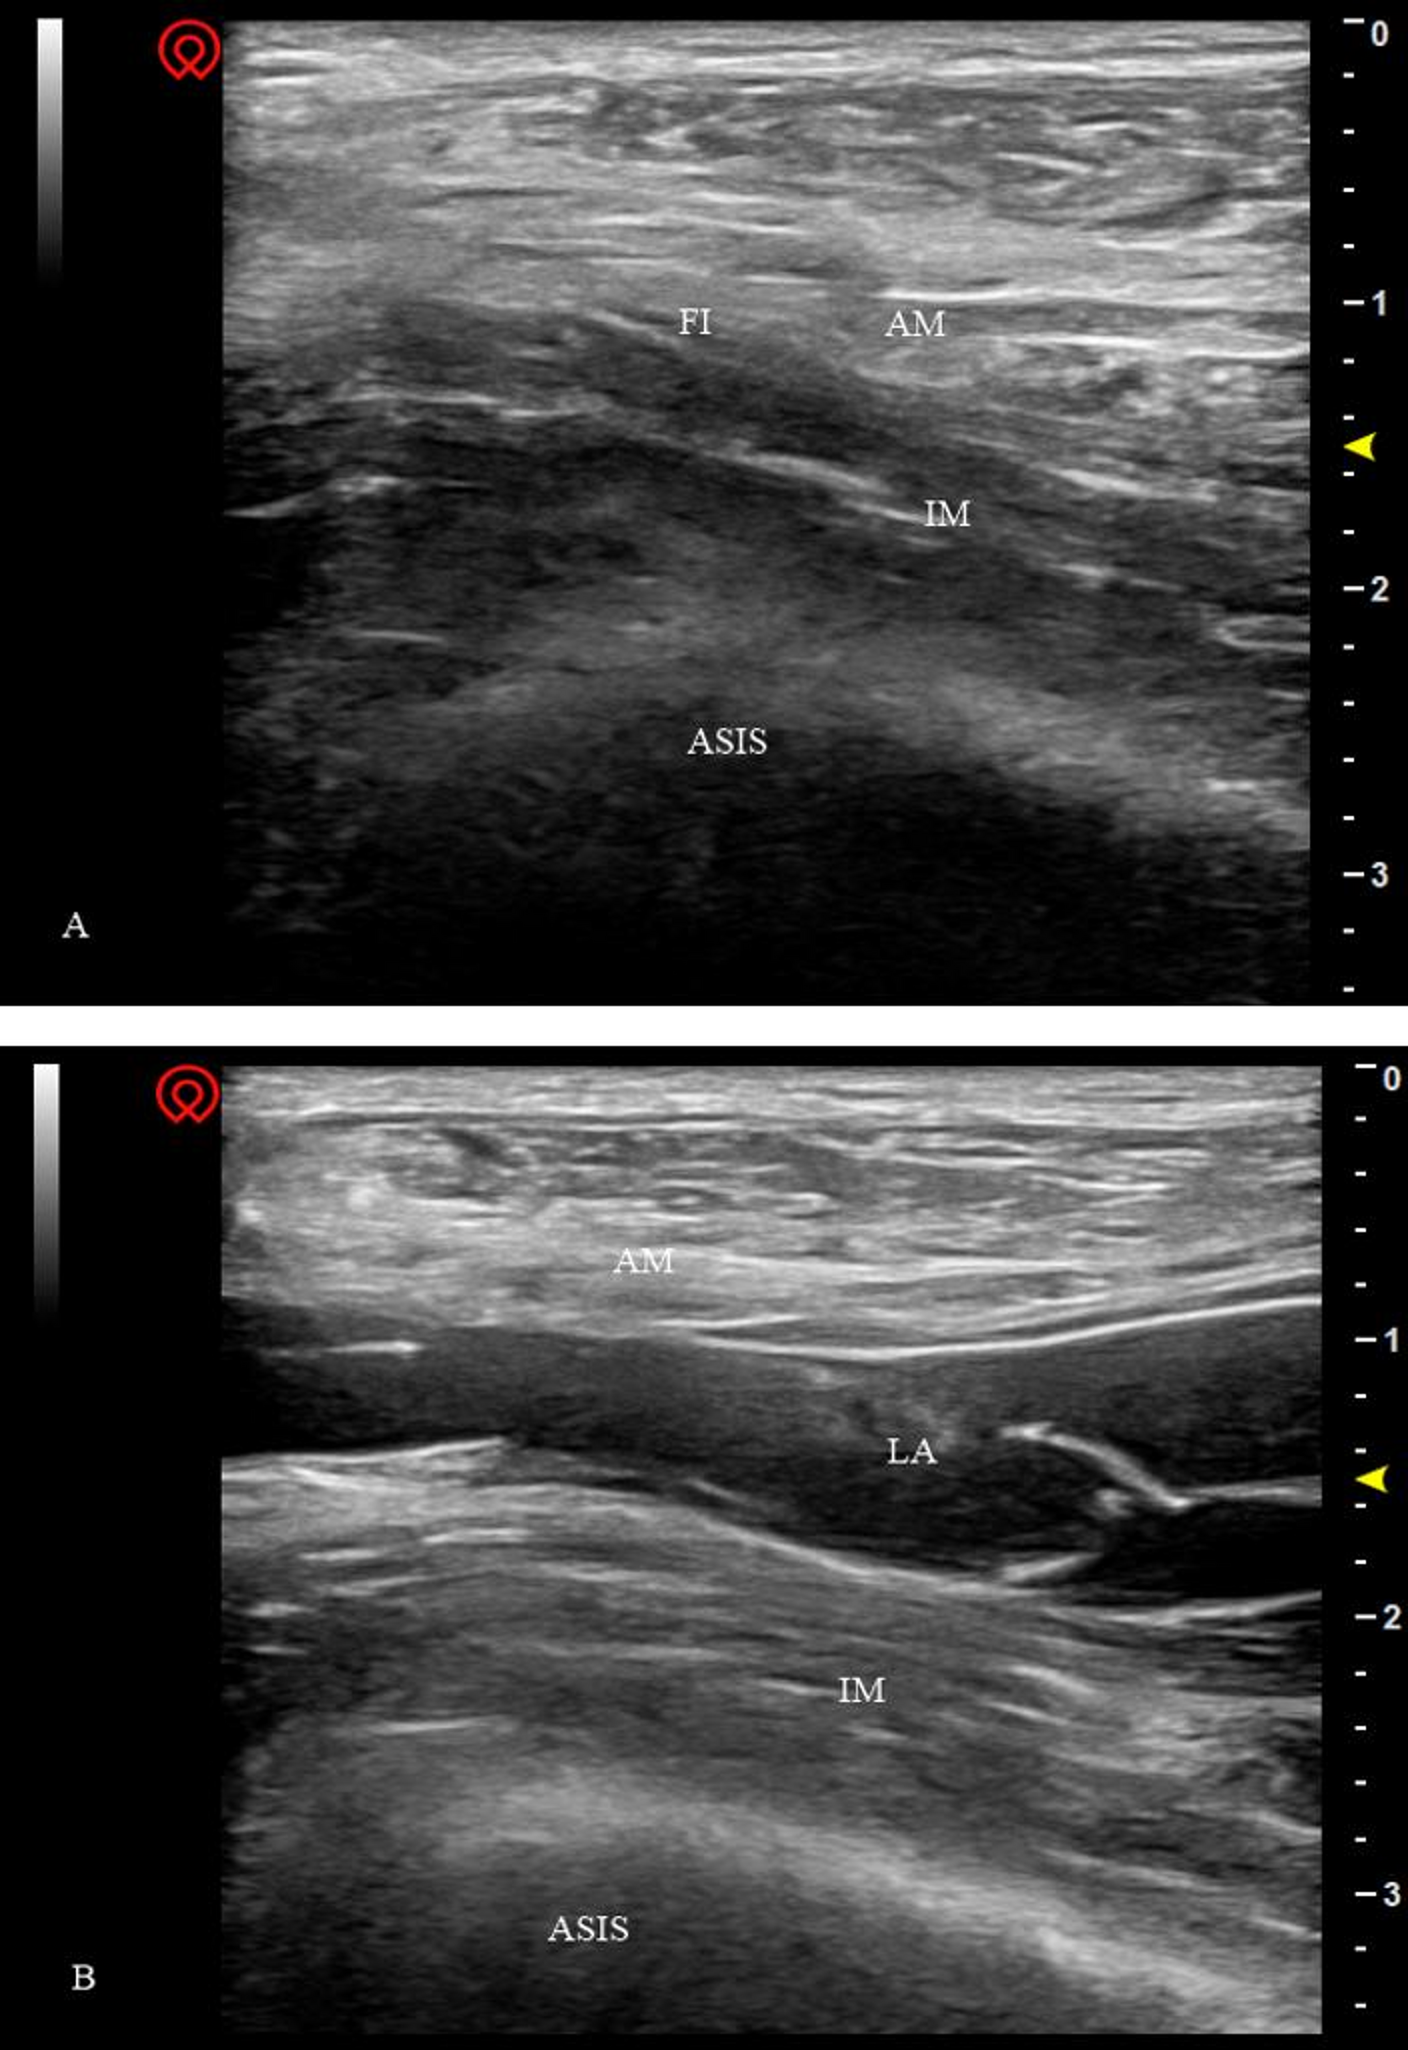

Fig. 1

Ultrasound-guided supra-inguinal FICB. (A) ultrasound image of pre-injection, (B) ultrasound image of post-injection. ASIS: anterior superior iliac spine, AM: abdominal muscles, FI: fascia iliaca, IM: iliacus muscle, LA: local anesthetic, FICB: fascia iliaca compartment block.